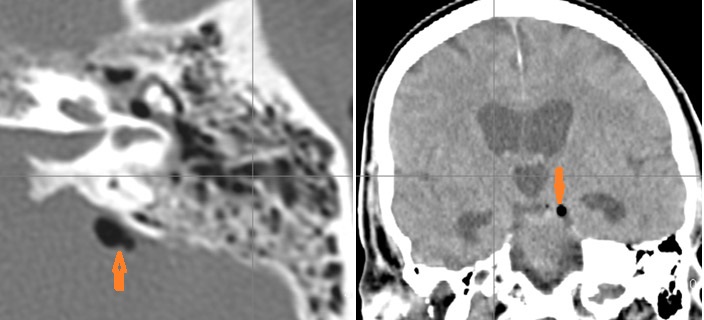

There is a subperiosteal abscess along the outer margin of the mastoid portion of the temporal bone.

There is gas in the subarachnoid space or otherwise intracranial.

There is evidence of thrombosis, thrombophlebitis or other occlusive or inflammatory process of the sigmoid sinus, transverse sinus, the vein of Labbe’ or jugular bulb

There is evidence of thrombosis, thrombophlebitis or other occlusive or inflammatory process of jugular vein.

There is a subperiosteal, subdural or epidural abscess along the floor of the middle cranial fossa or along the inner surfaces of the petrous portion of the temporal bone.